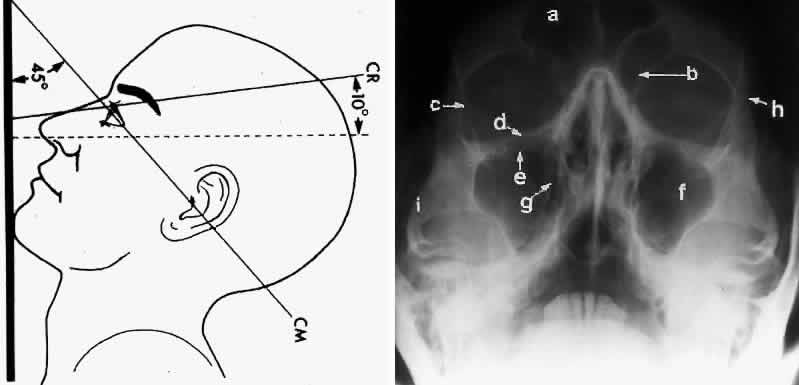

WATERS PROJECTION

In an attempt to improve the visualization of the maxillary and ethmoid sinuses, in 1915 Waters and Waldron7 described a radiographic projection (Fig. 2) that eliminated the overlapping shadows of the dense petrous ridge of the temporal bone. Waters projection is created by placing the chin of the patient on the x-ray cassette with the canthomeatal line (the line that connects the lateral canthus and the external auditory meatus) at 37 degrees to 45 degrees.5,6 This orientation is accomplished if the nose of the patient is approximately 0.5 to 1.5 cm above the x-ray plate.7,8 A mnemonic is—the patient raises the chin up to sip water.

Fig. 2. A. Schematic showing positioning for a Waters projection. (CM, canthomeatal line; CR, central ray) B. Radiograph of a Waters projection. The petrous ridge lies below the maxillary sinus. (a, frontal sinus; b, medial orbital wall; c, innominate line; d, inferior orbital rim; e, orbital floor; f, maxillary antrum; g, superior orbital fissure; h, zygomatic-frontal suture; i, zygomatic arch) (A; Rao VM, Gonzalez CF: Plain film radiography and polytomography of the orbit. In Gonzalez CF, Becker MH, Flanagan JC [eds]: Diagnostic Imaging in Ophthalmology, pp 1–7. New York, Springer Verlag, 1986)

Waters view provides the best image of the maxillary antrum and good images of the orbital rim, orbital floor, zygomatic bones and arches, lesser wing of the sphenoid, and infraorbital foramen. This view is useful to the clinician in orbital floor fracture assessment because of the clear image of the orbital floor and the underlying maxillary sinus. The floor of the orbit should form a continuous radiographic line with the lateral wall of the orbit. Confusion can occur regarding the location of the orbital floor and its relationship to the orbital rim. The orbital floor is located inferior to the orbital rim not in the same plane, because of the orientation of the patient's head in Waters projection. A soft tissue density in the roof of the maxillary sinus or opacification of the floor of the sinus suggests an orbital floor disruption.